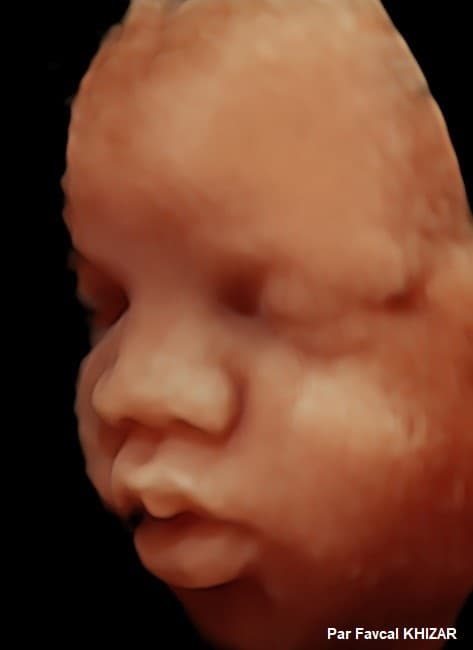

Mis à jour lundi 15 novembre à 12h22 Cédric Jubillar sortiratil de prison? La dysplasie de la hanche est un problème qui est parfois remarqué chez les bébés, et parfois chez les enfants, au moment où ils apprennent à marcher On l'appelle parfois » hanches clicky « , parce que si vous bougez les hanches d'un bébé atteint de dysplasie de la hanche, vous pouvez sentir un petit clic Habituellement, la